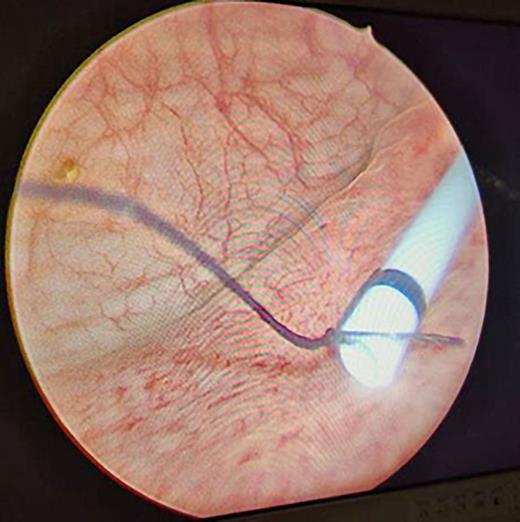

With considerable curiosity, we have read a recent article by Korkes and associates [1]. The article’s focus was on the medical management of stent-related symptoms, specifically the use of alpha antagonists, antimuscarinics, and PDE inhibitors either separately or in combination to lessen the symptoms associated with stents. The distal end of the DJ stent is known to cause pain and voiding symptoms, which is one of the causes contributing to stent-related symptoms [2]. Symptoms can be greatly reduced with a small modification to the ureteral stent. The traditional DJ stent’s lower coil is cut, and its lower end is stitched with a 5-0 mersilk (Fig. 1). Having placed it under fluoroscopy supervision (Fig. 2), we then bring the suture beyond the urethra and sew it to the labia majora in females and the glans penis in males (Fig. 3). We ask the patient to come to the outpatient department on the day of the stent removal. In the office environment itself, we cut the thread and pull the stent together with the thread under all hygienic circumstances. This method can greatly lessen the symptoms associated with the stent while also saving the patient a great deal of money and time. The evidence in favor of our position comes from a trial [3] in which the DJ stent’s distal coil was taken out for a custom-made distal coil that had a 0.3 Fr suture that reached the bladder and shown lower SRS and improved tolerance.

Suture (5-0 mersilk) tied to the distal end of ureteral stent.